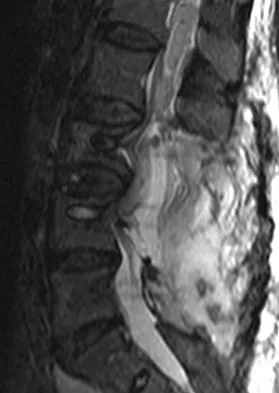

A 65-year-old man with ankylosing spondylitis has neck pain after falling back over his lawnmower, striking his thoracic spine, and forcing his neck into extension. Examination reveals subtle weakness of the intrinsics and finger flexors at approximately 4+/5. Initial management consists of immobilization in a rigid collar, and placing his head in the anatomic position. Radiographs reveal a subtle extension fracture of the lower cervical spine. Approximately 6 hours after the injury, he reports increasing paresthesias in his upper and lower extremities, and examination now shows his intrinsics are 2/5, finger flexors are 3/5, and his triceps are now weak at 4/5 on manual motor testing. In addition, his lower extremities now show weakness in both dorsal and plantar flexion of the ankle in the range of 4/5. Repeat radiographs appear unchanged. An MRI scan is shown in Figure 2. Management should now consist of

It is not uncommon for patients with ankylosing spondylitis to sustain extension-type fractures, most typically of the cervicothoracic junction. These fractures can appear nondisplaced or minimally displaced initially, making them difficult to diagnose. Because there is no mobility between vertebrae, fractures tend to occur more like those of a transverse fracture of a long bone. In addition, the vertebral bodies are vascular and their canals are relatively enclosed, making them vulnerable to epidural bleeding. The MRI scan reveals an epidural hematoma located posteriorly on the cord; therefore, the treatment of choice is surgical evacuation and a posterior laminectomy. Because of the intrinsic instability of such fractures at the time of the laminectomy, internal fixation and stabilization with a posterior fusion is warranted. A simple laminectomy will only increase instability, and control is unlikely with halo vest immobilization. An anterior procedure will not effectively treat the problem given the location of the hematoma. Consideration can be given to methylprednisolone and observation; however, this will not eradicate the problem. Bohlman HH: Acute fractures and dislocations of the cervical spine. J Bone Joint Surg Am 1979;61:1119-1142.